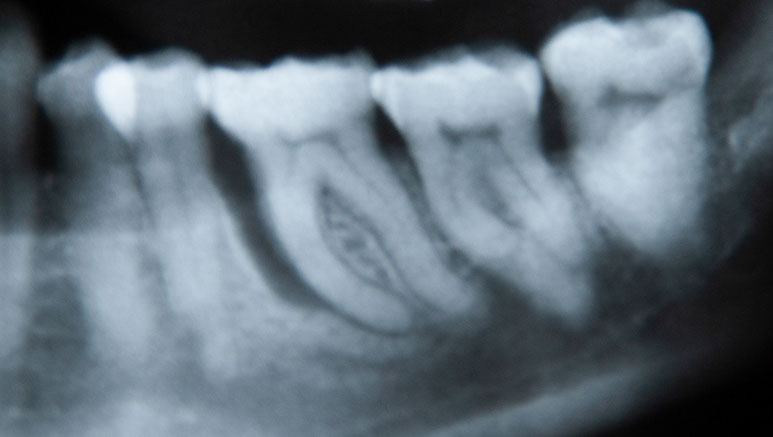

• OPG (Orthopantomogram - X-ray overview)